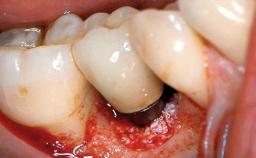

A 66-year-old patient presented because of retention loss of the tooth-supported FDP in the right maxilla (x-13-x-11). The mandibular full-arch implant-supported reconstruction (x-i34-i33-x-x-x-x-i43-i44-x) had suffered extreme wear. His medical history revealed high blood pressure, controlled with anti-hypertensive medication. The patient was a light smoker (2 to 3 cigarettes per day). The existing reconstructions had been performed alio loco about five years previously. That treatment had taken an extensive amount of time, and as early as during the fabrication of the reconstructions, multiple complications had occurred with the provisionals.